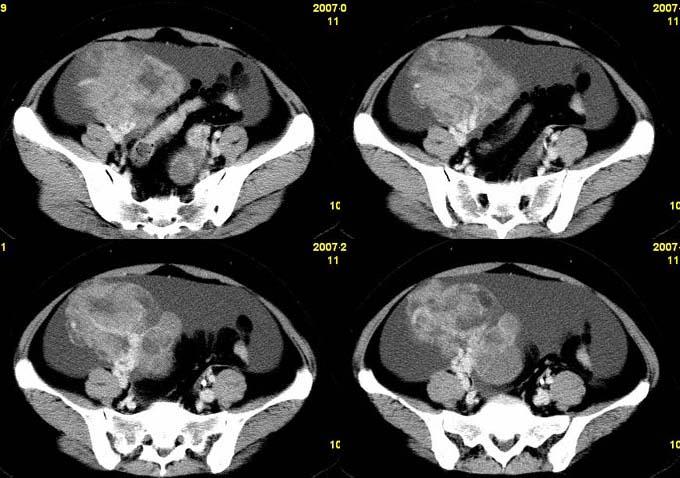

【病例】卵巢颗粒细胞瘤1例ct影像表现

卵巢粘液性囊腺癌1例ct影像

卵巢巨大肿瘤一例

卵巢囊腺癌(ovarian cystadenocarcinoma)ct病例(图文